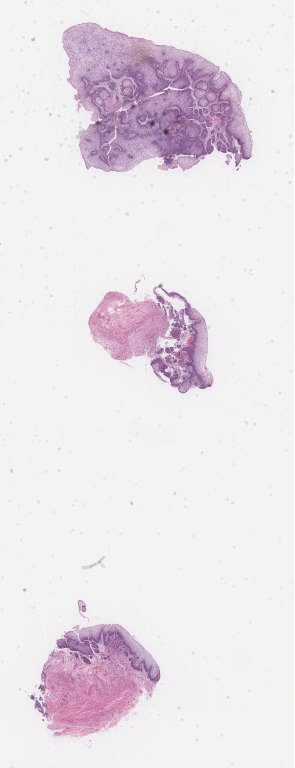

1415060.svs

40X